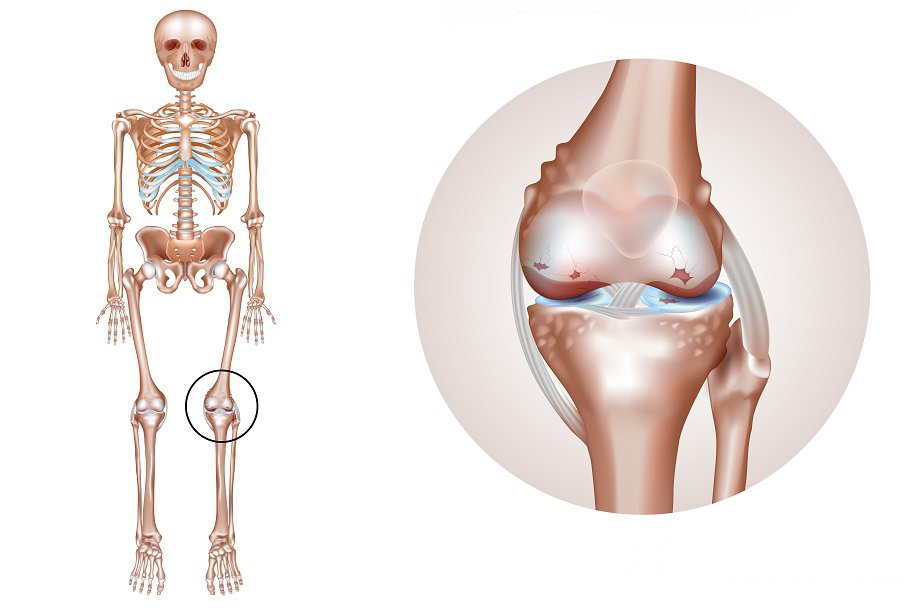

Артрит – это дегенеративно-дистрофическое заболевание соединительной ткани, поражающее суставной аппарат в совокупности с прилежащими тканями и вспомогательными структурами.

Артрит коленного сустава – распространенное дегенеративное заболевание опорно-двигательного аппаратаДля артрита характерны:

Гонартрит, как любое другое дегенеративное заболевание суставов, развивается вследствие дисбаланса между процессами синтеза и деградации в хрящевой и прилегающей костной тканях, приводящего в итоге к разрушению хряща.

Если в норме процессы новообразования превалируют, то при артритах данное равновесие смещается в сторону нарастания дистрофии и последующей дегенерации тканей. Первоначальные изменения на клеточном уровне приводят к нарушению тканевого гемостаза, видоизменяется тонкая структура хряща коленного сустава (выявляются очаги помутнения, истончения и разволокнения, микротрещины и разрывы). Ввиду происходящих структурных перестроек хрящ теряет эластичность, страдает его амортизационная функция, нарушается взаиморасположение сочленяющихся поверхностей, усугубляя деградацию.

Компенсаторно, в ответ на истончение хрящевой прослойки, начинается уплотнение и разрастание прилегающей костной ткани, формируются костные выросты, шипы, осложняющие адекватное функционирование коленного сустава и усугубляющие течение заболевания.